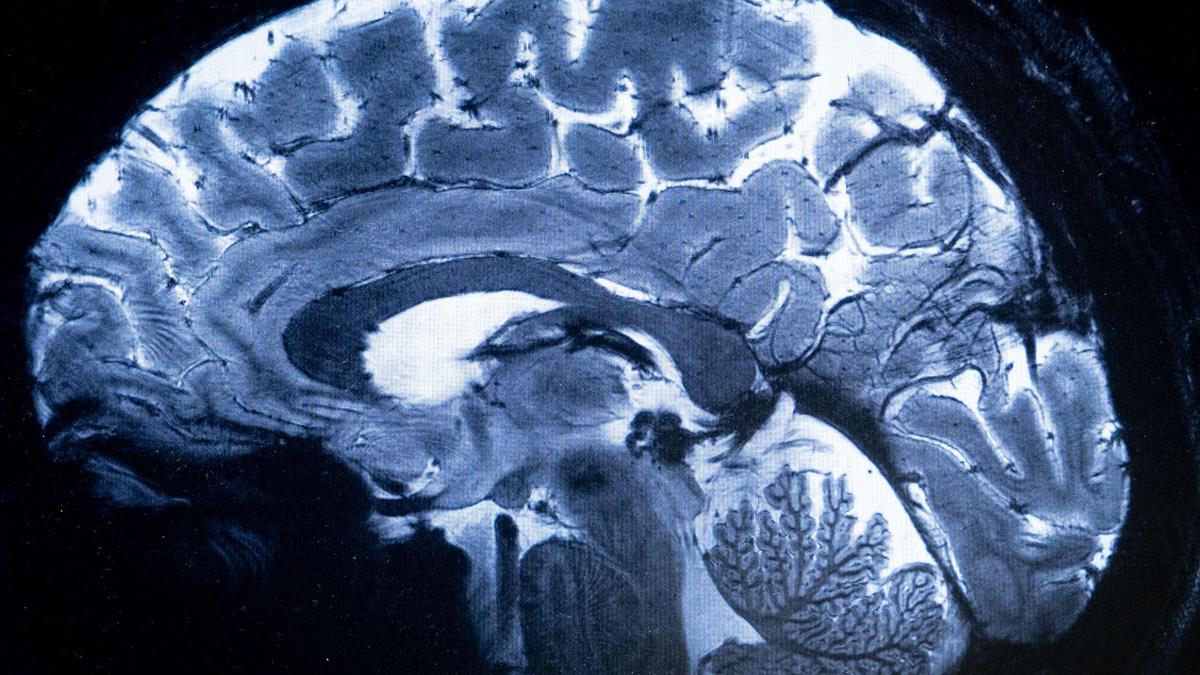

What Role Does Amyloid Beta Play in Alzheimer’s?

New research suggests Alzheimer’s arises not simply from plaques forming in the brain, but from one protein interfering with the normal job of another.